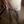

快来接好孕了!宝宝现已29周了,已知男女,这是28周+4天的B超单子

后壁,胎心129~132之间,肚子经常摸起来硬硬的,胎动很频繁,很活波的那种性格吧,我没有特别喜欢的口味,以前不吃甜的,红枣和鸡蛋都一样,吃一口就会干呕,现在却能吃甜食,红枣吃好几个都没问题,最纳闷的是居然爱吃肉,就是肥肉的那种,酸的,辣的都吃,不怎么忌口,除了闻不了炒的葱。有一样的孕妈没?